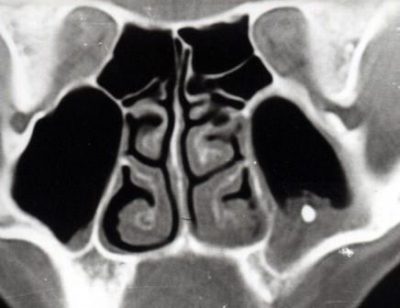

Только на рентген снимке или на экране компьютера при томографии можно обнаружить проблему.

- рентген снимок, который показывает не только наличие тела, но и пневматизацию (наличие воздуха),

- применение компьтерной томографии,

Пневматизация пазух – это не заболевание, а термин. С помощью него врачи характеризуют явления на снимке рентгена или на экране при томографии.

Пневматизация – уровень заполнения пазух воздухом, который при нормальном состоянии двигается без препятствий по носовым проходам.

На снимке можно заметить, что пневматизация:

- сохранена,

- снижена,

- повышена.

В первом случае, нет отклонений от нормы и скорее всего, причина болезни не в постороннем предмете.

Если инородное тело присутствует в гайморовой пазухе, то на это укажет пониженный уровень пневматизации. При этом воздух с трудом циркулирует, что приводит к уменьшению поставок кислорода в организм.